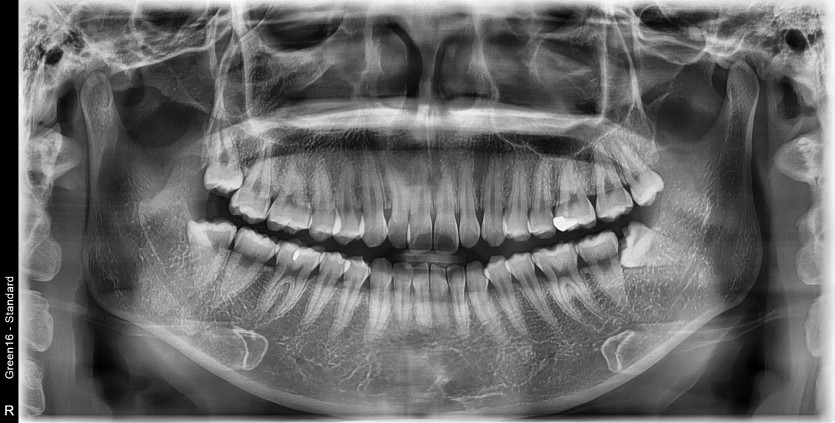

#18,28,38,48 사랑니 발치

구강 외과 전문의가 당일 발치했습니다.